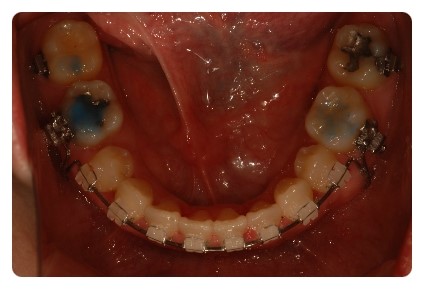

하악도 이제 조금밖에 안남았어요

그런데 닫히고나면 어느정도까지 더 장치를 하고있어야될까요 ??

오래걸렸는데 ㅠㅠ 금방 돌아가버리진않겠죠 ;;